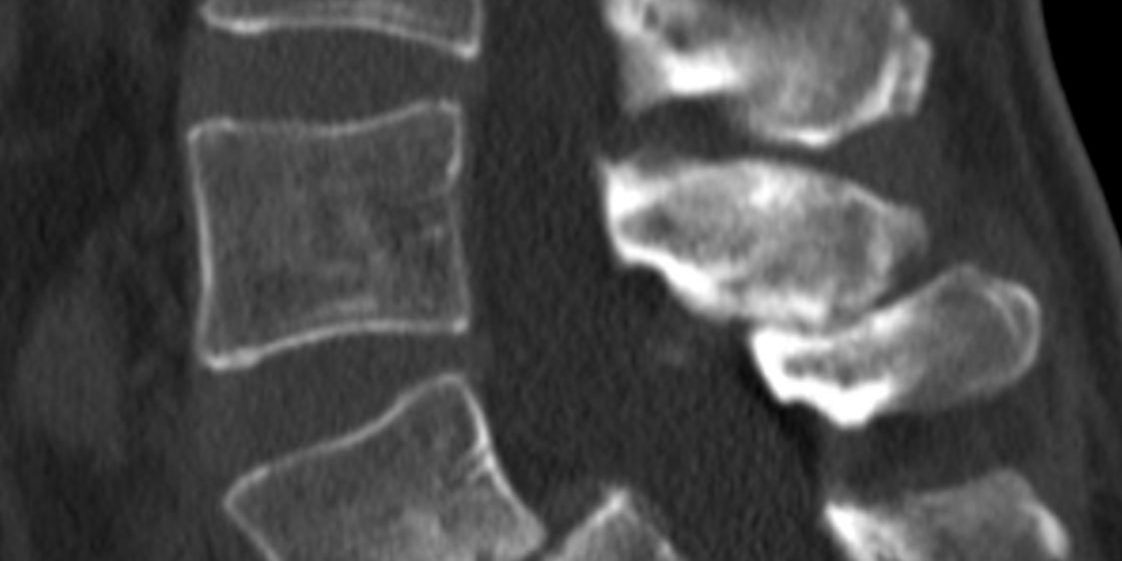

Ο απεικονιστικός έλεγχος ανέδειξε σπονδυλολίσθηση 2ου βαθμού σε έδαφος σπονδυλόλυσης στο ύψος Ο5-Ι1.

Διενεργήθη διαδερμική (ελάχιστα επεμβατική) σπονδυλοδεσία στο επίπεδο Ο5-Ι1